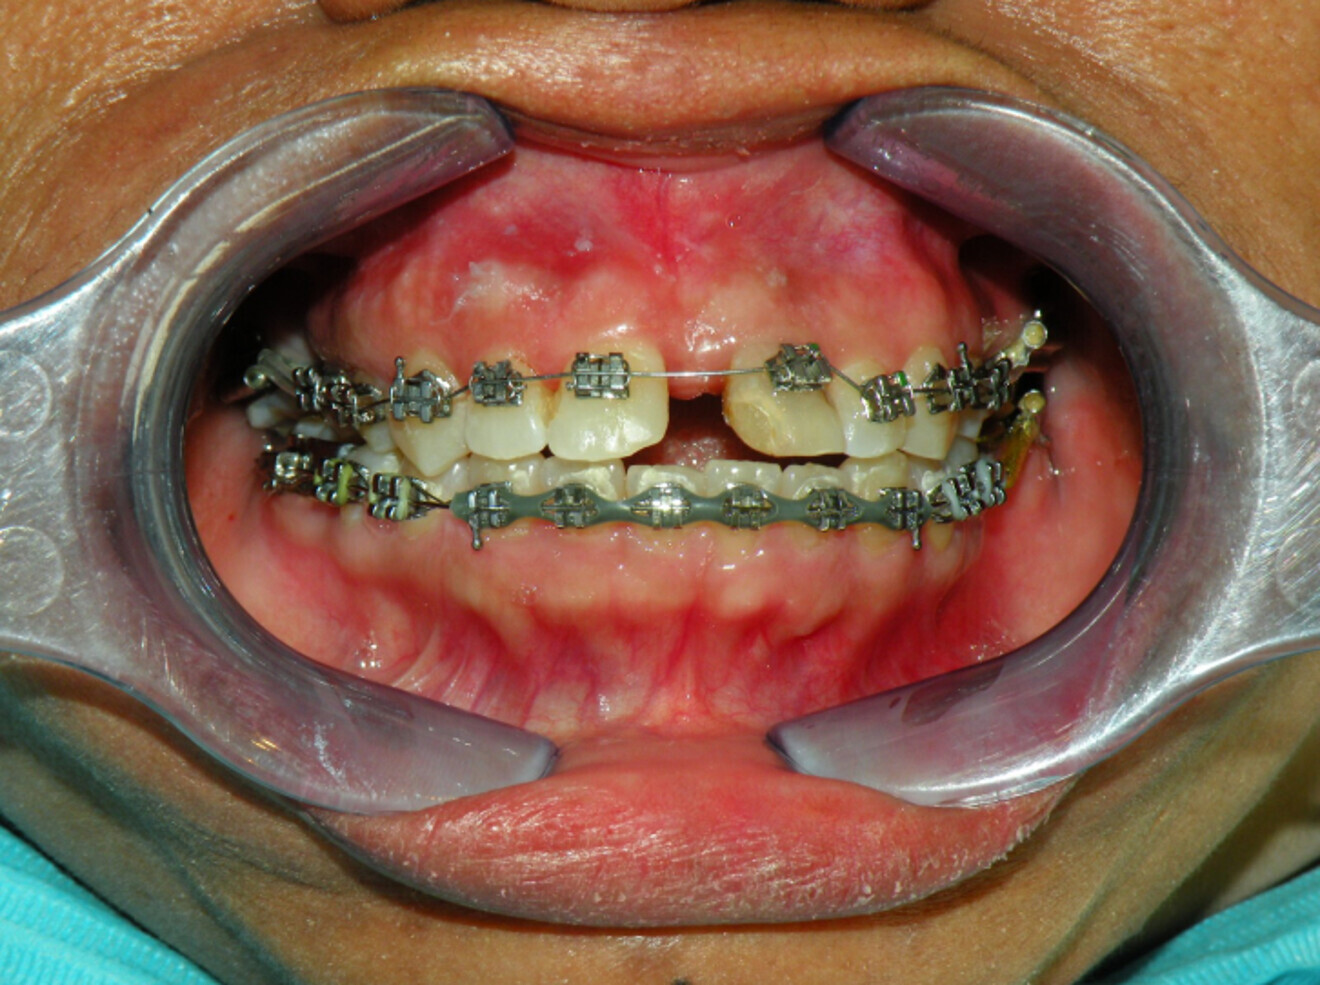

Treatment Plan:

– Upper lower conventional metal MBT brackets.

– Posterior spaces to be maintained for future implants.

– 2-unit bridge before debonding.

– Essix retainer upper lower for retention.

Fig. 12a: Lower arch bonded first to collapse in pursue of overjet and overbite.

Fig 12b:  Upper arch bonded once spaces in lower arch managed.